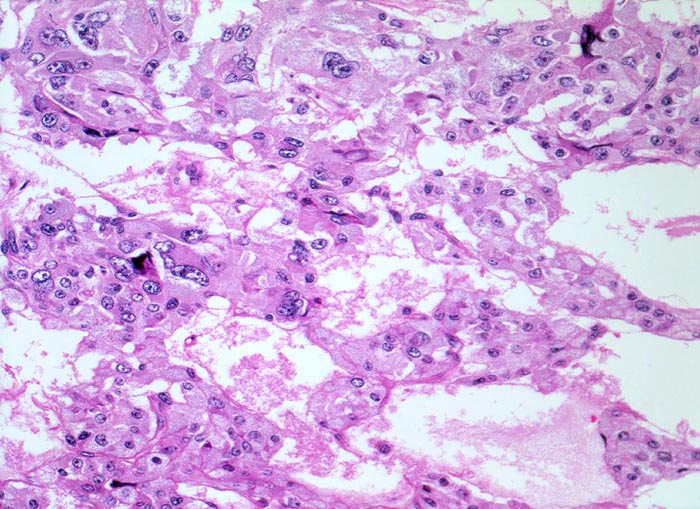

Phaeochromozytom

Nebenniere

«Zellballen» aus teils spindelig konfigurierten, grossen Tumorzellen. In den Bindegewebssepten um die Zellballen lassen sich zahlreiche dilatierte Blutgefässe nachweisen.

Der Patient klagt über rezidivierende Kopfschmerzen seit zirka zwei Monaten. In letzter Zeit hat er Alcacyl genommen, jedoch ohne Erfolg. Die Computertomographie des Abdomens zeigt einen 5cm grossen Tumor im Bereich der rechten Nebenniere. Die Familienanamnese für multiple endokrine Neoplasien (MEN) ist bland.

Histologie

50